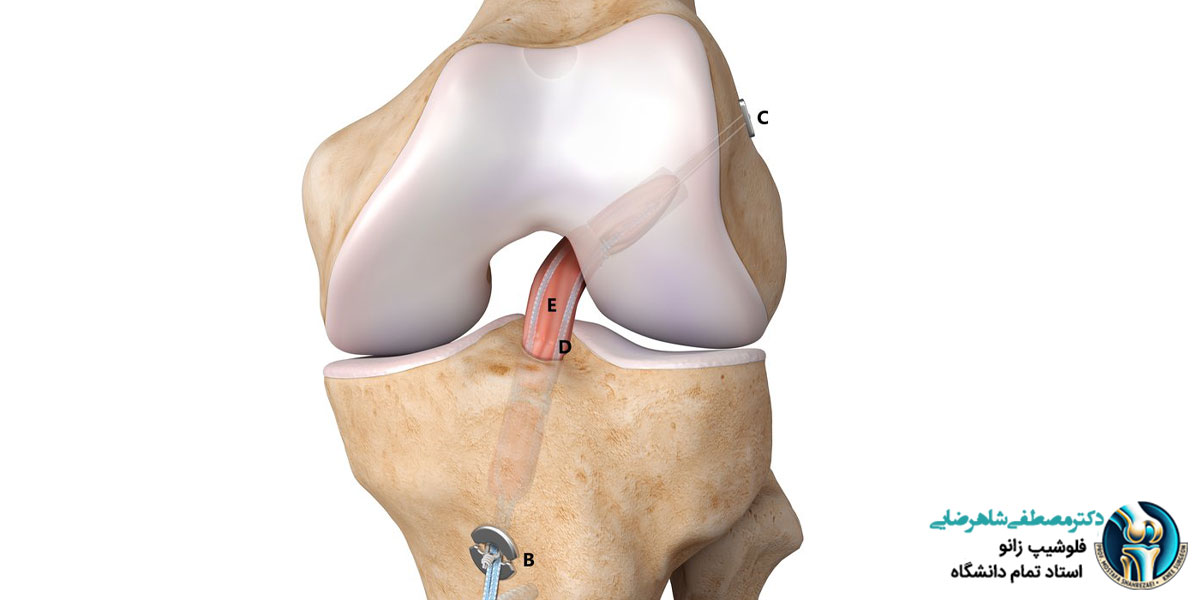

آسیب به رباط صلیبی زانو یکی از شایع ترین مشکلاتی است که برای بسیاری از افراد طی اتفاقات مختلف پیش می آید. این نوع آسیب می تواند باعث درد شدید و محدود شدن حرکت زانو و همچنین مانع انجام کارهای روزمره شود. درمان رباط صلیبی معمولا نیاز به جراحی دارد، اما قبل از جراحی، آمادگی های خاصی باید ایجاد شود تا بتوان به بهترین نتیجه رسید. این آمادگی ها شامل مشاوره با پزشک متخصص برای ارزیابی وضعیت آسیب، بررسی گزینه های درمانی مختلف و برنامه ریزی برای فیزیوتراپی قبل از جراحی است. همچنین، بیمار باید از مراحل بعد از جراحی و دوره نقاهت نیز اطلاعات کافی داشته باشد تا سریع تر و بهتر آن دوره را طی کند.

برای تشخیص آسیب به رباط صلیبی زانو، پزشک ابتدا معاینه فیزیکی انجام می دهد. در این معاینه، پزشک از شما می خواهد که زانو را در جهت های مختلف حرکت دهید تا ببیند آیا درد، محدودیت حرکتی یا احساس لغزش وجود دارد. پس از معاینه، ممکن است پزشک از شما بخواهد که یک آزمایش اشعه ایکس هم انجام دهید. با این که این آزمایش می تواند مشکلاتی مانند شکستگی استخوان ها را نشان دهد، اما به خودی خود نمی تواند آسیب های رباط ها را کامل شناسایی کند. به همین دلیل، پزشک معمولاً از MRI استفاده می کند که دقیقاً وضعیت رباط ها و بافت های نرم زانو را نشان می دهد و آسیب وارد شده به رباط صلیبی را به وضوح مشخص می کند. علاوه بر این، پزشک ممکن است تست هایی مثل تست لچمن را برای بررسی ثبات زانو انجام دهد. در برخی موارد دیگر نیز پزشک آزمایش های خونی انجام می دهد تا مطمئن شود که مشکلی مانند عفونت که بر روند درمان تأثیر گذار است، وجود ندارد.

بعد از آسیب به رباط صلیبی، اولین کاری که باید انجام شود، کاهش درد و تورم و برگشت دامنه حرکت زانو به حالت طبیعی است. این کار ممکن است با توجه به شدت آسیب از چند هفته تا چند ماه زمان ببرد. معمولا بهتر است جراحی رباط صلیبی در عرض ۳ تا ۶ ماه بعد از آسیب انجام شود چون اگر جراحی به تاخیر بیفتد، احتمال بروز آسیب های دیگر مثل پارگی منیسک یا مشکلات غضروفی بیشتر می شود. اگر جراحی خیلی دیر انجام شود هم ممکن است مشکلاتی مانند ضعیف شدن عضلات زانو، کاهش انعطاف پذیری و آسیب به دیگر قسمت های زانو ایجاد شود.